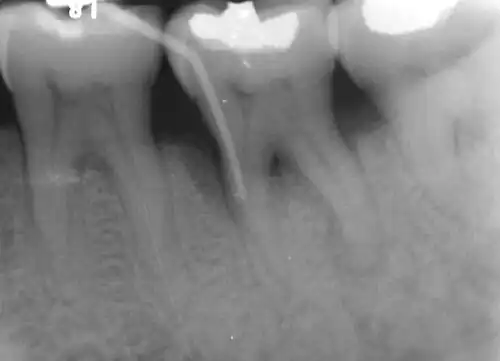

Diagnosis

Nabers probe is used to check for furcation involvement clinically. Recently, cone beam computerised technology (CBCT) has also be used to detect furcation.[5] Periapical and interproximal intraoral radiographs can help diagnosing and locating the furcation.

In dentistry, a furcation defect is bone loss, usually a result of periodontal disease, affecting the base of the root trunk of a tooth where two or more roots meet (bifurcation or trifurcation). The extent and configuration of the defect are factors in both diagnosis and treatment planning.[1]

The distance between the cementoenamel junction (CEJ) and the furcation entrance is called the root trunk length. This distance plays an important role in furcation defects because the deeper the furcation entrance is within the bone, the more bone loss necessary before the furcation becomes exposed.

For mandibular first molars, the mean root trunk length is 3 mm on the buccal aspect and 4 mm on the lingual aspect.[2] The root trunk lengths for mandibular second and third molars are either the same or slightly greater than for first molars, although the roots may be fused.